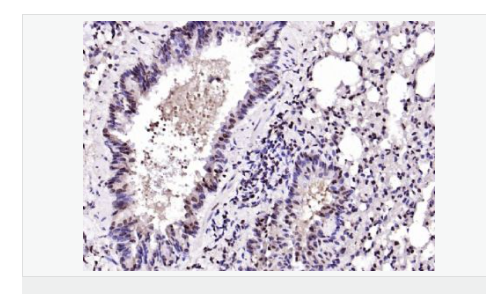

| 產品應用 | ELISA=1:5000-10000 IHC-P=1:100-500 IHC-F=1:100-500 IF=1:100-500 (石蠟切片需做抗原修復) not yet tested in other applications. optimal dilutions/concentrations should be determined by the end user. |

| 產品介紹 | The protein encoded by this gene is a member of the BTG/Tob family. This family has structurally related proteins that appear to have antiproliferative properties. This encoded protein might play a role in neurogenesis in the central nervous system. Two transcript variants encoding different isoforms have been found for this gene. [provided by RefSeq, Aug 2008]. Function: Overexpression impairs serum-induced cell cycle progression from the G0/G1 to S phase. Subunit: Interacts with KCNMA1 tetramer. There are probably 4 molecules of KCMNB1 per KCNMA1 tetramer. Subcellular Location: Membrane; Multi-pass membrane protein. Tissue Specificity: Abundantly expressed in smooth muscle. Low levels of expression in most other tissues. Within the brain, relatively high levels found in hippocampus and corpus callosum. Similarity: Belongs to the KCNMB (TC 8.A.14.1) family. KCNMB1 subfamily. SWISS: Q14201 Gene ID: 10950 Database links: Important Note: This product as supplied is intended for research use only, not for use in human, therapeutic or diagnostic applications |